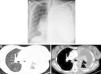

Case reportA 36-year-old light-smoking pregnant woman was admitted to hospital at 27 weeks gestation in August 2010 with a history of malaise, fatigue, exertional dyspnea, dry cough and left pleuritic chest pain since the second trimester of the gestation. No regular medication was reported. On physical examination, she appeared to have poor performance status (PS 3). Pulmonary auscultation revealed reduction of the breath sounds in the left lung field. Chest X-ray showed total left lung opacity with contralateral mediastinal deviation, suggestive of pleural effusion (Fig. 1A). A thoracocentesis and pleural biopsy were performed revealing the diagnosis of pleural invasion by lung adenocarcinoma. The immunohistochemical study showed CK7, CK8/18 and was napsin positive and negative for CK20, estrogens and progesterone receptors. The test for EGFR mutation (direct DNA sequencing) was negative.

After delivery, the patient underwent a thoracoabdominal CT which depicted a large left hilar mass with no plane of cleavage with vascular structures, multiple implants on mediastinal pleura, and a large volume of left pleural effusion (Fig. 1B), and multiple bone and liver metastases. First line chemotherapy with carboplatin plus oral vinorelbine (AUC 5 and 60mg/m2, respectively) was started on September 2010. Intravenous zoledronic acid was also prescribed. After 4 sessions of chemotherapy, despite some clinical improvement, there was progression of the disease with the spreading of bone disease and neurological symptoms of paraplegia and sphincter disruption (Fig. 2). Subsequently, the patient underwent second line chemotherapy with pemetrexed (500mg/m2), and thoracic spine (T4–T10) radiotherapy (30Gy/12 sessions), but without clinical efficacy.